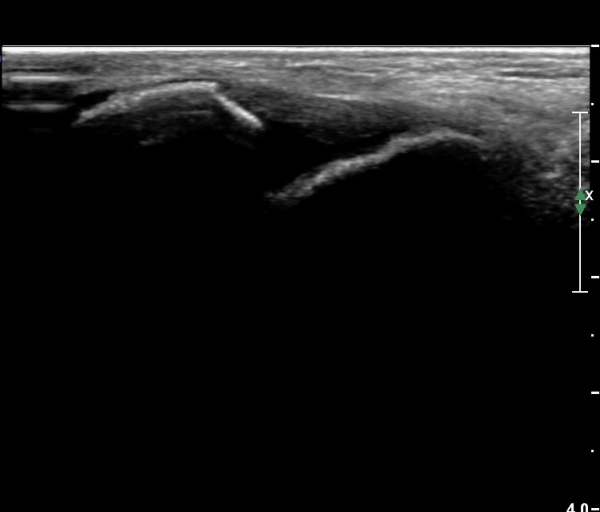

°ÇÃø °Å°ñºñ°ñÀδë Á¾´Ü¸é°Ë»ç¿¡¼­ Á¤»óÀûÀÎ ¼Ò°ßÀ» º¸À̰í(»çÁø 6),

°ÇÃø°ú ºñ±³Çϸé È¯ÃøÀÇ º´Àû ¼Ò°ßÀÌ ¶Ñ·ÈÇÏ´Ù(»çÁø 7).